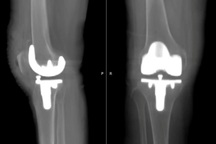

Ảnh chụp phim X-quang sau phẫu thuật thay khớp gối trái toàn phần (Ảnh: BVCC).

Ca phẫu thuật do TS.BS Nguyễn Hữu Mạnh, Giám đốc bệnh viện, cùng ThS.BSNT Vũ Đức Việt tiến hành. Ê-kíp sử dụng phương pháp gây tê tủy sống kết hợp kiểm soát đau đa mô thức giúp bệnh nhân tỉnh táo sau mổ. Đồng thời, kỹ thuật thay khớp ít xâm lấn giúp giảm tổn thương phần mềm, hạn chế mất máu. Các bác sĩ sử dụng loại khớp nhân tạo thế hệ mới bằng titanium và polyethylene có độ tương thích sinh học cao, tuổi thọ có thể kéo dài trên 20 năm. Toàn bộ quá trình phẫu thuật diễn ra thuận lợi, kéo dài khoảng 90 phút.

Sau mổ, bệnh nhân ổn định, ít đau, mạch huyết áp bình thường. Đặc biệt, chỉ sau 6 tiếng phẫu thuật, bà L. đã có thể ngồi dậy và bắt đầu tập đi với khung tập. Hiện bệnh nhân đã được xuất viện, có thể đi lại bình thường.